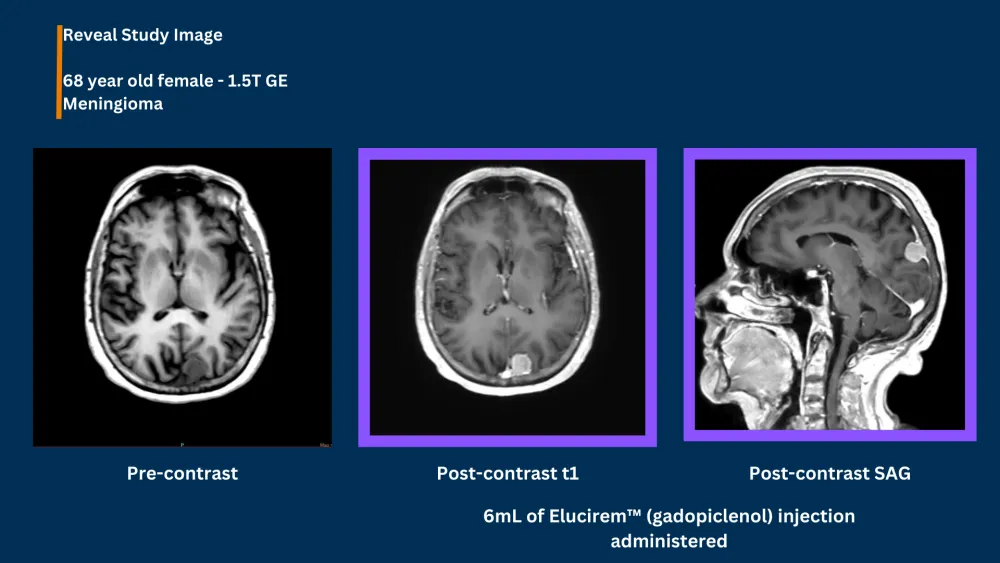

Guerbet Launches the EluciremTM (gadopiclenol) injection Reveal Image Challenge Click here for details Guerbet Launches the EluciremTM (gadopiclenol) injection Reveal Image Challenge… Elucirem™ (gadopiclenol) injection Reveal Image Challenge Elucirem (US) Clinical Studies Elucerim (gadopiclenol) injection Image Reveal Challenge Reveal Challenge Winners Want to take part in this challenge? Share your MRI images using ELUCIREM (gadopiclenol) injection. Click here for details